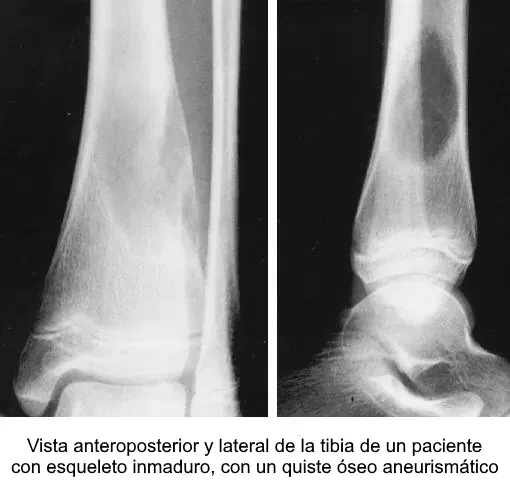

Ejemplo radiológico

3) Quiste óseo aneurismático (QOA)

2.1 Concepto y epidemiología

- Definición: lesión quística expansiva benigna con espacios sanguíneos separados por tabiques fibrosos con células gigantes y osteoide reactivo.

- Edad: predominio en <20 años.

- Localización: metáfisis de huesos largos y elementos posteriores vertebrales.

- Primario vs secundario: primario (frecuente); secundario a otra lesión (no “dar por hecho” en atípicos).

2.3 Radiología

- Rx: lítica, excéntrica, expansiva, septada; adelgazamiento cortical.

- TC/RM: niveles líquido-líquido (característico, no exclusivo); tabiques con realce.